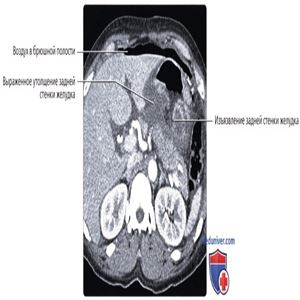

КТ с контрастированием, аксиальный срез: определяется язва задней стенки желудка с выраженным утолщением стенки желудка вблизи язвы. Кроме того, наблюдается обширное скопление газа в верхнем отделе брюшной полости. Сочетание этих признаков позволяет диагностировать прободную язву желудка.